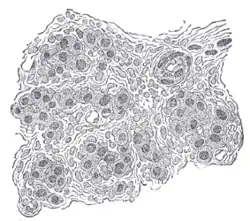

![]() Section of part of human carotid body. Highly magnified. Numerous blood vessels are seen in section among the cells. | |

頸動脈體含有兩種細胞球細胞:第一型球細胞(主細胞)及第二型球細胞(支持細胞)